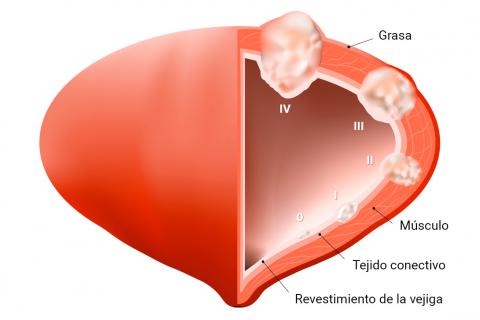

Un gran problema que se tiene con este cáncer es que, si eres mujer, el último diagnóstico que miran es el del cáncer, por lo que cuando se detecta, el músculo suele estar también con el tumor. El músculo de la vejiga es el encargado de mantener la orina en su sitio y liberarla cuando sea necesaria.

El diagnóstico y posterior tratamiento varía según la fase en la que se encuentre el tumor, si tiene ganglios dañados, las características de tamaño y extensión.

Si se coge en las primeras fases del cáncer se realiza un tratamiento curativo. Esto significa que se extirpa la parte de lesión y luego se valora si es necesario usar medicamentos de quimioterapia o inmunoterápicos.

Si el cáncer es más profundo necesitas que te extirpen la vejiga completa, incluyendo la próstata en el caso de los hombres.